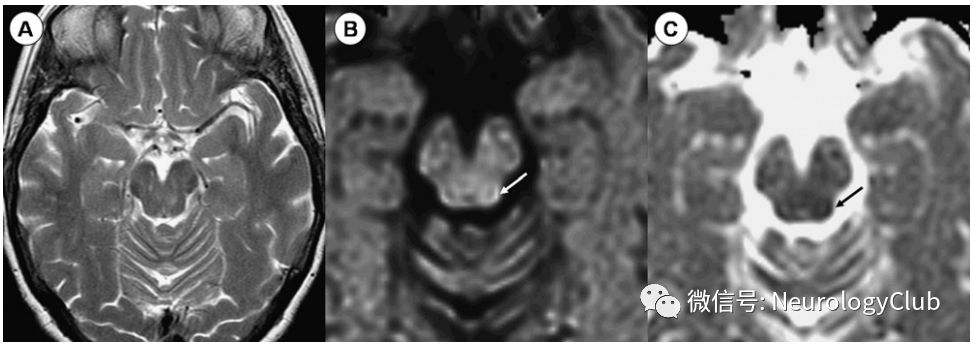

前内侧梗死(图4)导致偏瘫或半瘫、对侧共济失调、构音障碍、吞咽困难、眼球震颤,也经常出现同侧面肌麻痹。较少出现对侧本体感觉缺失,同侧眼球水平凝视麻痹及核间性眼肌麻痹。

图4:脑桥前内侧梗死;62岁患者,表现为左侧偏瘫,共济失调,构音障碍,吞咽困难,眼球震颤以及同侧水平凝视障碍;A:T2WI可见右侧脑桥轻微高信号;B-C:DWI和ADC证实急性脑桥前内侧部梗死